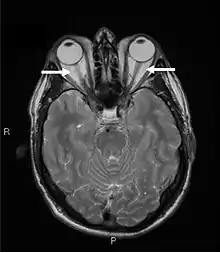

Magnetic resonance imaging of the orbits, showing congestion of the retro-orbital space and enlargement of the extraocular muscles (arrows), consistent with the diagnosis of Graves' ophthalmopathy.

Orbital imaging is an integral tool for the diagnosis of Graves' ophthalmopathy and is useful in monitoring patients for progression of the disease. It is, however, not warranted when the diagnosis can be established clinically. Ultrasonography may detect early Graves' orbitopathy in patients without clinical orbital findings. It is less reliable than the CT scan and magnetic resonance imaging (MRI), however, to assess the extraocular muscle involvement at the orbital apex, which may lead to blindness. Thus, CT scan or MRI is necessary when optic nerve involvement is suspected. On neuroimaging, the most characteristic findings are thick extraocular muscles with tendon sparing, usually bilateral, and proptosis.